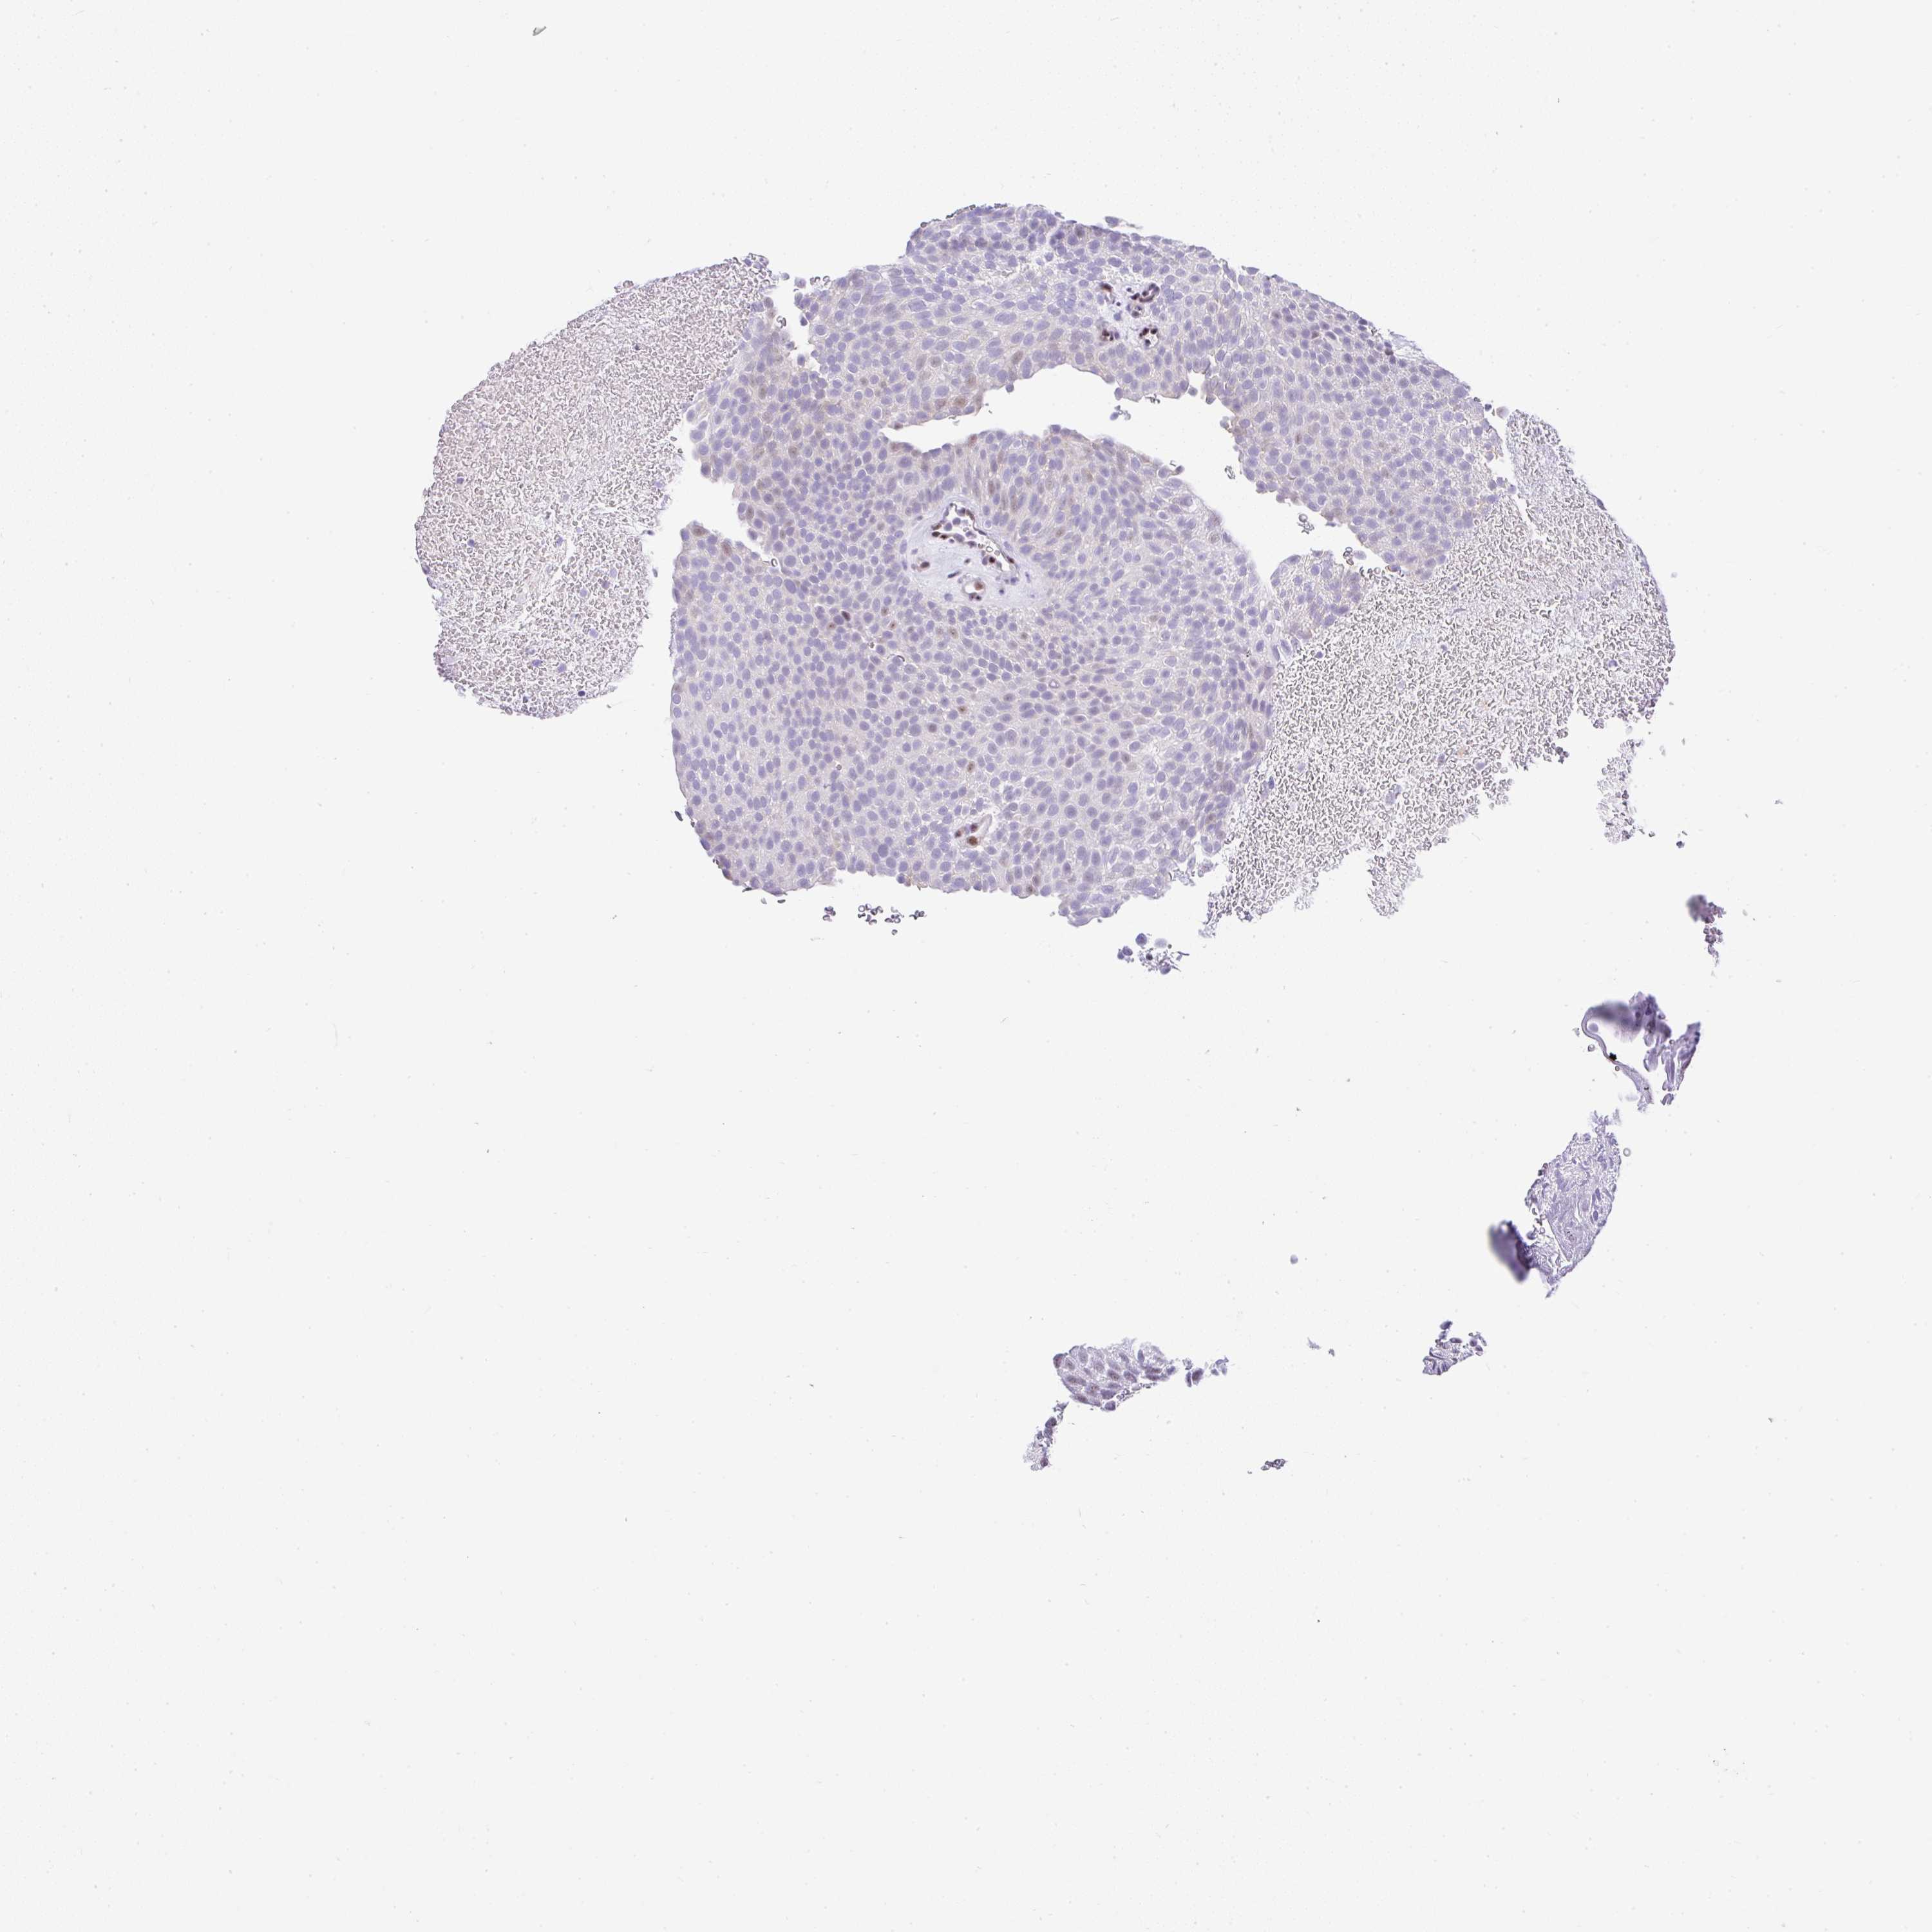

UROTHELIAL CANCER - Protein expressioni

A mouse-over function shows sample information and annotation data. Click on an image to view it in a full screen mode. Samples can be filtered based on level of antibody staining by selecting one or several of the following categories: high, medium, low and not detected. The assay and annotation is described here.

Antibody stainingi

Antibody staining in the annotated cell types in the current human tissue is reported as not detected, low, medium, or high, based on conventional immunohistochemistry profiling in selected tissues. This score is based on the combination of the staining intensity and fraction of stained cells.

Each image is clickable and will lead to virtual microscopy that enables deeper exploration of all samples and also displays staining intensity scores, fraction scores and subcellular localization as well as patient and tissue information for each sample.

Antibody HPA054798

Staining

High

Medium

Low

Not detected

Intensity

Strong

Moderate

Weak

Negative

Quantity

>75%

75%-25%

<25%

None

Location

Nuclear

Cytoplasmic/membranous

Cytoplasmic/membranous,nuclear

Urothelial carcinoma, High grade

Urothelial carcinoma, Low grade